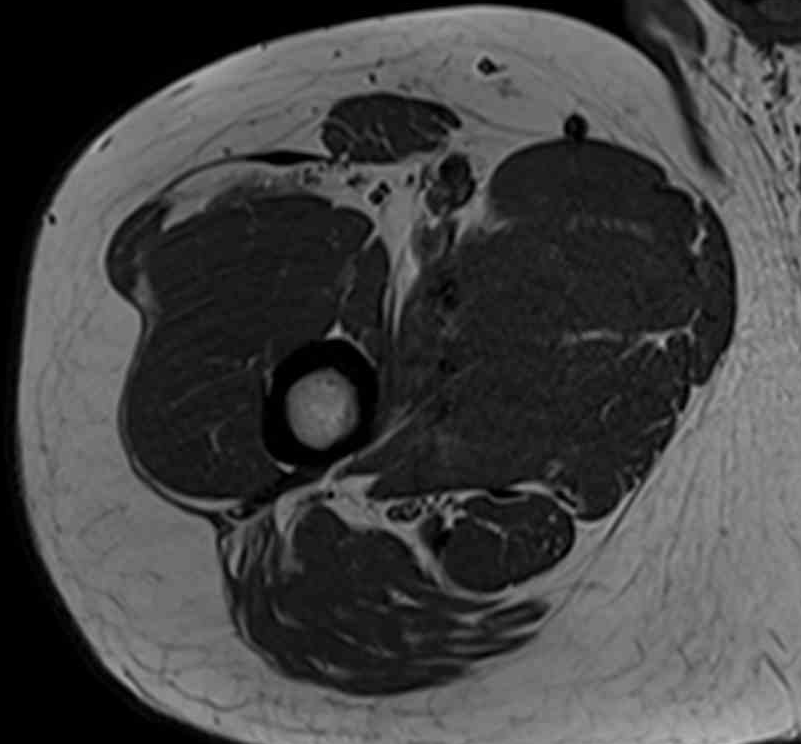

Normal central tendon